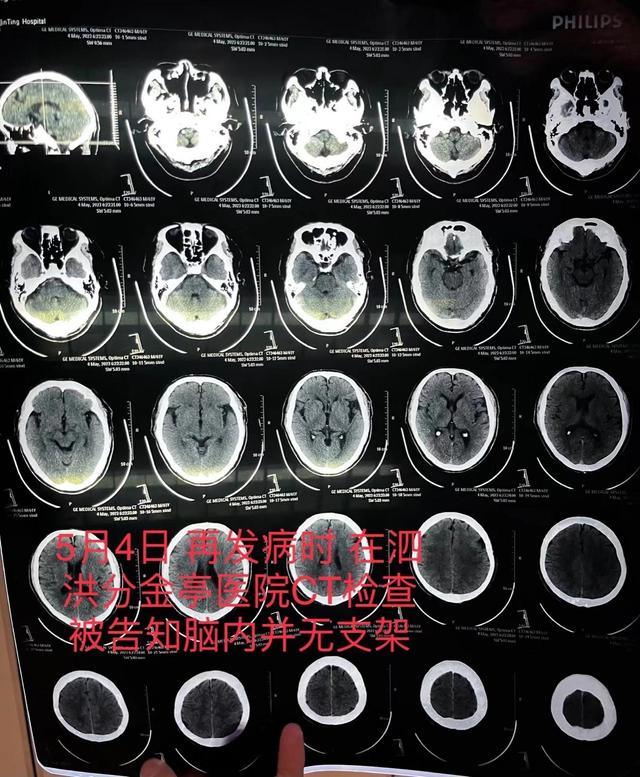

朱老汉在泗洪县分金亭医院的ct检查报告,显示颅内并无支架.朱先生供图